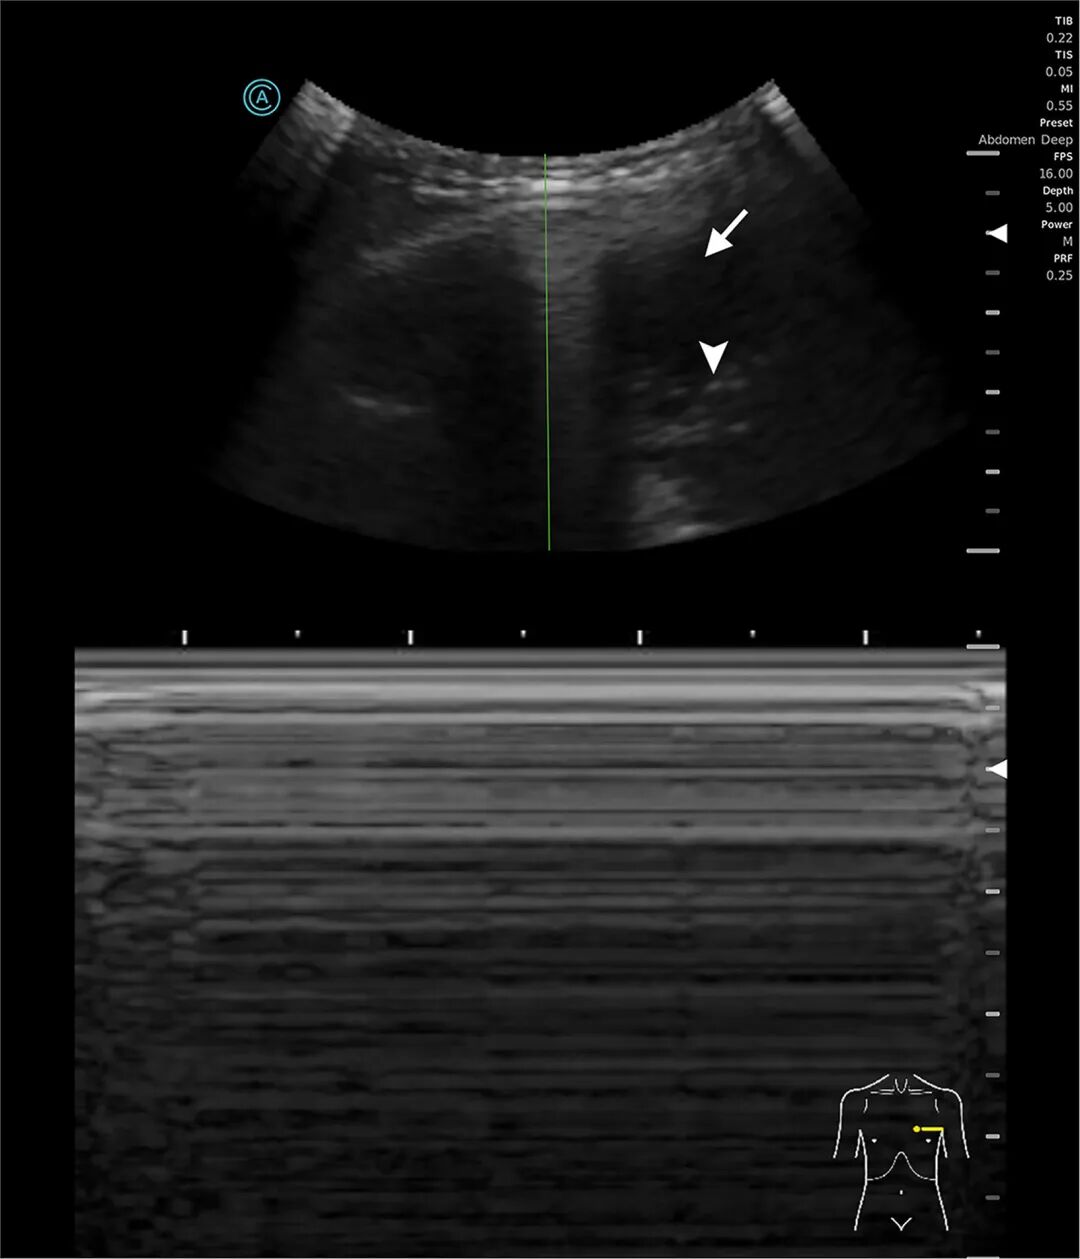

行床旁超声(图1)显示左侧大量胸腔积液

,可见浮游物,且肺滑动征消失。计算机断层扫描(CT)证实左侧广泛脓气胸

图1:左侧胸廓M型超声

图1超声显示气胸时平流层征(条形码征)。由于肺滑动征消失,M型超声图像全程表现为均匀的水平线(正常沙滩征模式消失)。胸膜线显示为清晰的高回声水平线。在B型图像右侧可见低回声胸腔积液(箭头)及游离气体(三角箭头),符合脓气胸表现。肺滑动征消失同时合并可见胸腔积液提示复杂胸膜病变。图2显示左侧大量胸腔积液,并可见气液平面(三角箭头),提示胸膜腔内存在游离气体。非重力依赖性游离气体(箭头)在积液最上方形成清晰、光滑的气液界面,符合液气胸(胸腔积液合并气体蓄积)表现。塌陷的左肺向上受压(星号)。上述表现符合脓气胸伴大量胸腔积液。

超声可见胸腔积液伴浮游物征且肺滑动征消失,提示脓胸。厌氧菌产生的气体可解释气胸的形成。